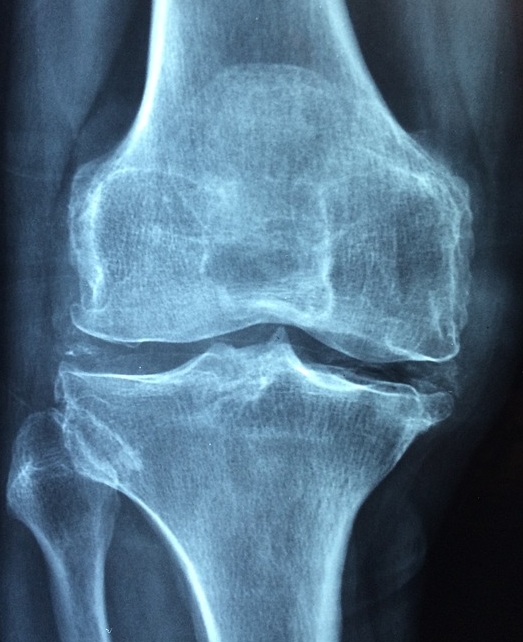

무릎 관절염 초기증상

무릎 관절염은 퇴행성 관절염이 가장 흔합니다. 나이가 들면서 연골이 닳고, 무릎이 붓거나 아픈 증상이 나타납니다.

- 계단을 오르내릴 때 무릎이 아프고 힘이 빠짐

- 장시간 앉아 있다가 일어날 때 무릎이 뻣뻣함

- 무릎에서 '뚝뚝' 소리가 나거나, 부종이 생김

- 심한 경우 무릎 모양이 O자로 변형됨

저희 부모님도 무릎이 아파서 병원을 찾았는데, 초기에 관리하면 연골 손상을 늦출 수 있다고 하시더라고요. 약물치료와 운동을 병행하면 효과가 좋다고 하니 꾸준한 관리가 필요합니다.